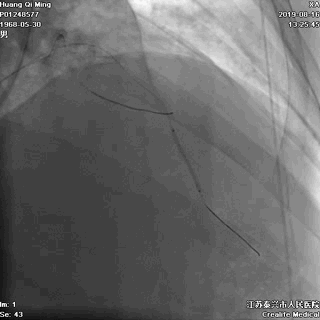

8atm,2.0*10 切割球囊对斑块进行切割

16atm,NC球囊对斑块进行预处理